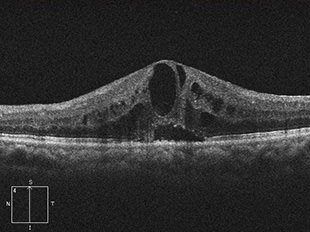

糖尿病黄斑浮腫

糖尿病黄斑浮腫は、糖尿病網膜症の合併症として発症します。網膜の細い血管に瘤ができてもろくなり、血管から血液中の成分がもれだし、それが網膜内にたまり浮腫(むくみ)を起こします。特に視機能において重要な部位である黄斑部に浮腫が生じると、ものが見えづらくなります。さらに浮腫が黄斑の中心部にまで及ぶと、著しい視力障害をきたし、かすんで見えたり、見えないところができたり、歪みが生じたりします。

治療前

治療後

治療前 OCT

治療後 OCT